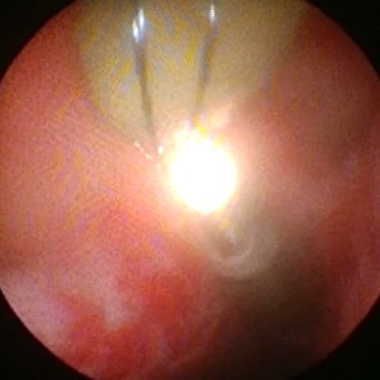

尿路結石

泌尿器科学会の推奨する尿路結石治療ガイドラインに準じて治療オプションの提示・決定を原則としています。尿路結石には体外衝撃波結石破砕術や内視鏡を使った手術を行っており、多くは通院治療で行っています。体外衝撃波では治療困難な症例に対しては内視鏡手術(経尿道的腎尿管砕石術)を施行します。ホルミウムレーザー砕石装置および細径内視鏡が導入されており、内視鏡手術の安全性と有効性が高くなっています。